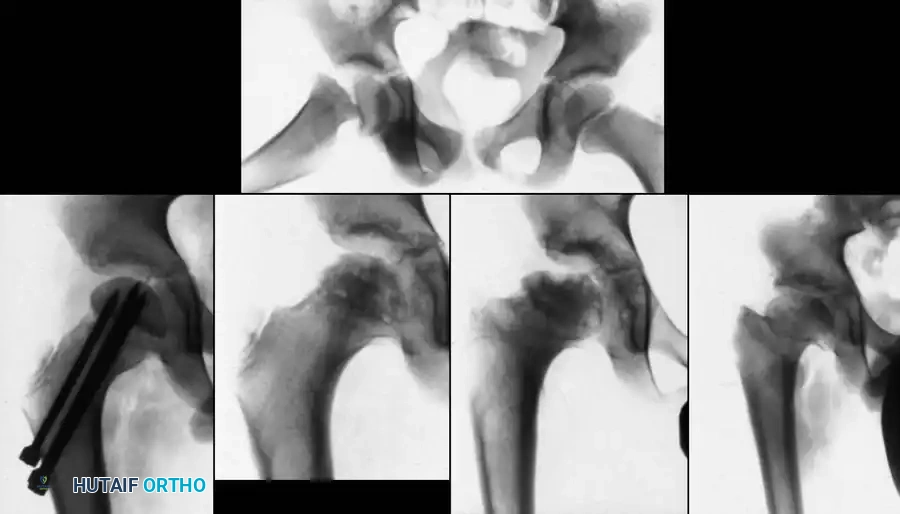

Fig. 1: Premature closure of the triradiate cartilage following severe pelvic and hip trauma, illustrating the profound impact of injury on the growing pediatric pelvis.

Fig. 4: Severe fracture-dislocation of the hip, demonstrating the high-energy nature of these injuries.

Fig. 5: Radiographic progression of a complex pediatric hip injury requiring extensive reconstruction.

Fig. 6: Long-term follow-up showing severe ankylosis and traumatic arthritis secondary to osteonecrosis.